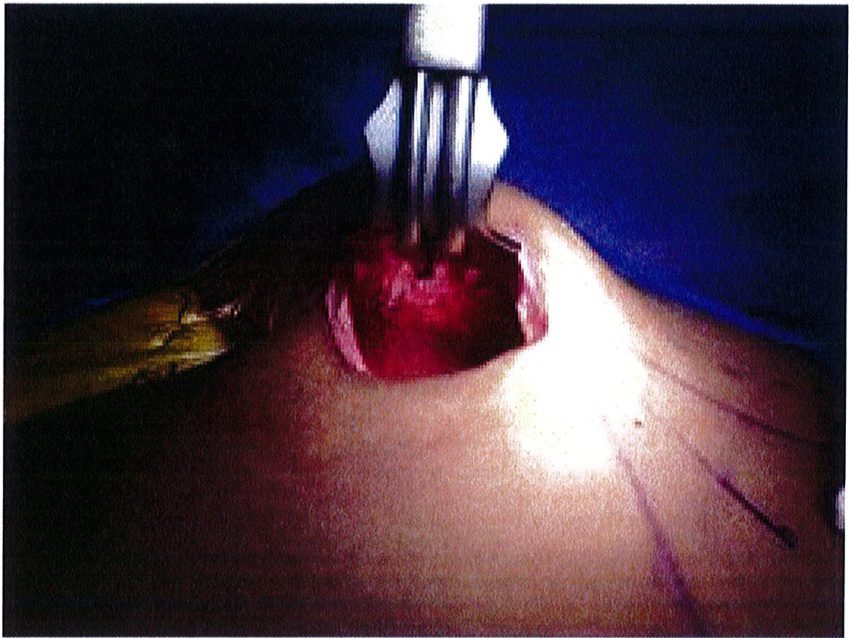

Dụng cụ bóc tách hai đầu tù, hình tròn được sử dụng để phân tách mặt phẳng vô mạch đã được bộc lộ bằng cách tiêm dung dịch trước đó, nhằm bảo tồn tối đa vách và lớp cân mạc. Nên thực hiện bóc tách từ trong ra ngoài, từ trên xuống dưới với một dụng cụ banh có đèn sợi quang (Hình 10). Để tách các vách ngăn, sử dụng một cây bóc tách dài có một đầu nhọn hoặc kéo dài (Hình 11). Các nhánh động mạch mông trên, mông dưới và một số mạch nuôi cho vùng cân mạc được đốt điện. Hãy chắc chắn

Extent of area undermined

Hình. 12. Bóc tách mặt phẳng dưới cơ trước khi đặt sizer để ước tính vị trí, kích thước khối implant khi đặt vào (From de la Pena JA, Rubio OV, Cano JP, et al. Sub- fascial Nâng mông. Clin Plast Surg 2006;33:412; đã xin phép trước khi đăng tải.)

Hình. 13. Bóc tách lớp dưới cân của một tử thi và nâng lên để quan sát. Đường rạch lớn như thế này chỉ với mục đích quan sát và minh họa quá trình phẫu thuật, không áp dụng trong lâm sàng. Trong thực tế, một đường rạch tiêu chuẩn chỉ dài 6-7 cm. (From de la Pena JA. Subfascial technique for Nâng mông. Aesthet Surg J 2004;24:268; đã xin phép trước khi đăng tải.)

Hình. 14. Sau khi hoàn thành việc đặt túi, hãy đặt 1 sizer vào để đánh giá tính cân đối và thể tích khoảng không gian bên trong đó. Chú ý khối implant phải vừa khít với túi. (From de ia Pena jA, Kubio ÜV, Cuno JP, et al. Subfascial Näng mong. Clin Plast Surg 2006; 33:414; đã xin phép trước khi đăng tải.)